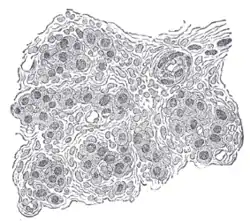

![]() Section of part of human carotid body. Highly magnified. Numerous blood vessels are seen in section among the cells. | |